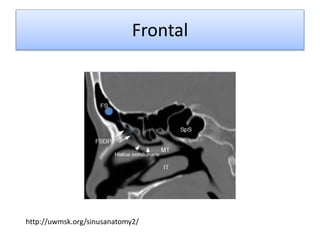

Frontal

http://uwmsk.org/sinusanatomy2/

-2 celdas

-Casi siempre asimétricas

- 10% mas de 2 celdas

-Divididas por un septo óseo fino

-Normalmente no en línea media

-Formado por la neumatizacion

del receso frontal hacia el hueso

- Formación hasta los 12 años